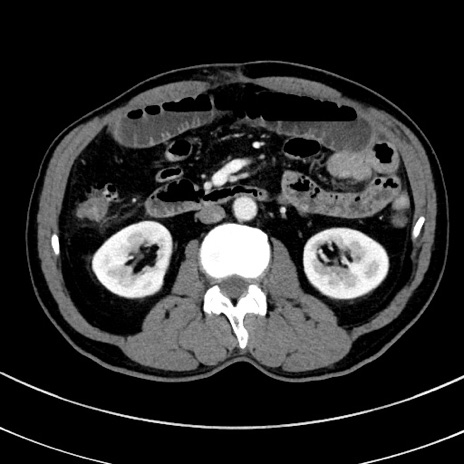

冠状断像

【症例】 60歳代男性

【主訴】 黒色吐物

【現病歴】 4日前から嘔気自覚、2日前の朝食後にも嘔気あり、自分で手で嘔吐反射起こし嘔吐したところ血が混ざっていたため受診。

【既往歴】 5年前汎発性腹膜炎を伴う急性虫垂炎で手術、高血圧、前立腺肥大症、高脂血症

【身体所見】 腹部正中に手術癩痕あり 腹部平坦・軟圧痛なし膨満感あり

【データ】WBC 8400、CRP 4.54